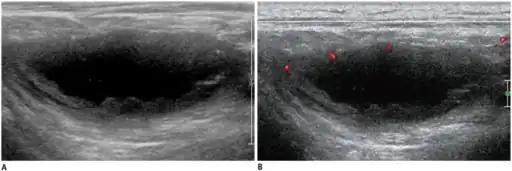

The diagnosis of tuberculous lymphadenitis may require a biopsy.[2] Other possible diagnostic steps include: positive tuberculin test, chest radiograph, CT scan, cytology/biopsy (FNAC), AFB staining, and mycobacterial culture.

- Cold abscess

- 'Collar stud' abscess